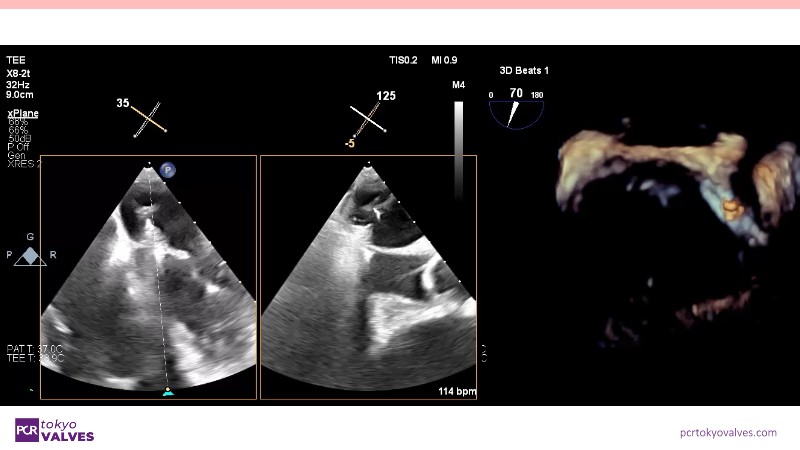

Explore the latest advancements in TEER therapy with this PCR Tokyo Valves 2025 session dedicated to MitraClip. Through expert-led case discussions, gain a deeper understanding of complex scenarios, including restricted posterior leaflet in functional mitral regurgitation, commissure lesion (A3P3), and MitraClip combined with Amulet.

- To learn about atrioventricular valve morphology and the associated treatment challenges with TEER